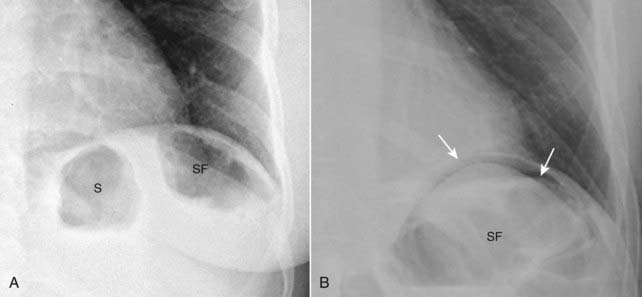

Figure 15-4 Normal left hemidiaphragm (A) and free air under hemidiaphragm (B).

Close-up views of the left upper quadrant demonstrate the difficulty in recognizing free air beneath the left hemidiaphragm because of the normal location of gas-containing structures such as the stomach (S) and splenic flexure (SF). There is no free air seen in (A) but the other patient (B) does have a crescent of free air (solid white arrows). It is easier to recognize free air beneath the right hemidiaphragm because there is usually no air present above the liver on the right side.